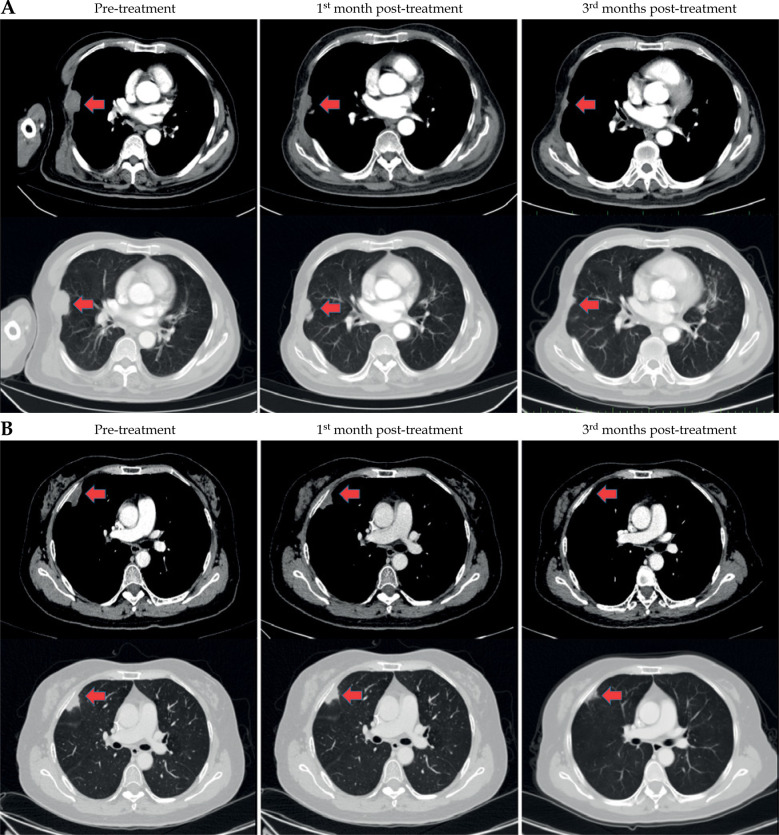

Material and methods: This single-centre retrospective cohort study involved 21 patients with pleural/chest wall malignant tumours treated between January 2024 and January 2025. All patients underwent HDR ISBT (30 Gy in a single fraction). Treatment included CT-guided needle implantation, three-dimensional dose optimisation (Oncentra system), and adherence to Radiation Therapy Oncology Group dose constraints for organs at risk (OARs). Efficacy endpoints included objective response (Response Evaluation Criteria in Solid Tumours v1.1), pain relief (Numerical Rating Scale), and dosimetric comparison with virtual stereotactic body radiotherapy. Safety was assessed using the Radiation Therapy Oncology Group/European Organisation for Research and Treatment of Cancer toxicity criteria.

Results: The median follow-up duration was 7.48 months. The objective response rate (complete response + partial response) was 76.19%, with 28.57% achieving a complete response and 47.62% achieving a partial response. Pain relief was achieved in 87.5% of patients with pretreatment pain, with numerical rating scale scores decreasing from moderate to severe (median, 6) to mild (median, 3) at 1 month. No ≥ grade II complications (e.g. bronchopleural fistula, pneumothorax) occurred; only four patients experienced minor subcutaneous haemorrhage/emphysema. Dosimetric analysis showed a significantly higher target mean dose with ISBT than with stereotactic body radiotherapy (p < 0.001), while OARs doses (e.g. lungs, heart, spinal cord) remained within Radiation Therapy Oncology Group limits. Rib and chest wall dose exceedances were rare and clinically insignificant.

Conclusions: Computed tomography-guided 192Ir HDR ISBT offers safe, effective local control and rapid pain relief for pleural/chest wall tumours, demonstrating superior dosimetric conformity and lower toxicity to OARs. This minimally invasive approach is a viable option for patients unsuitable for surgery or external beam radiotherapy.